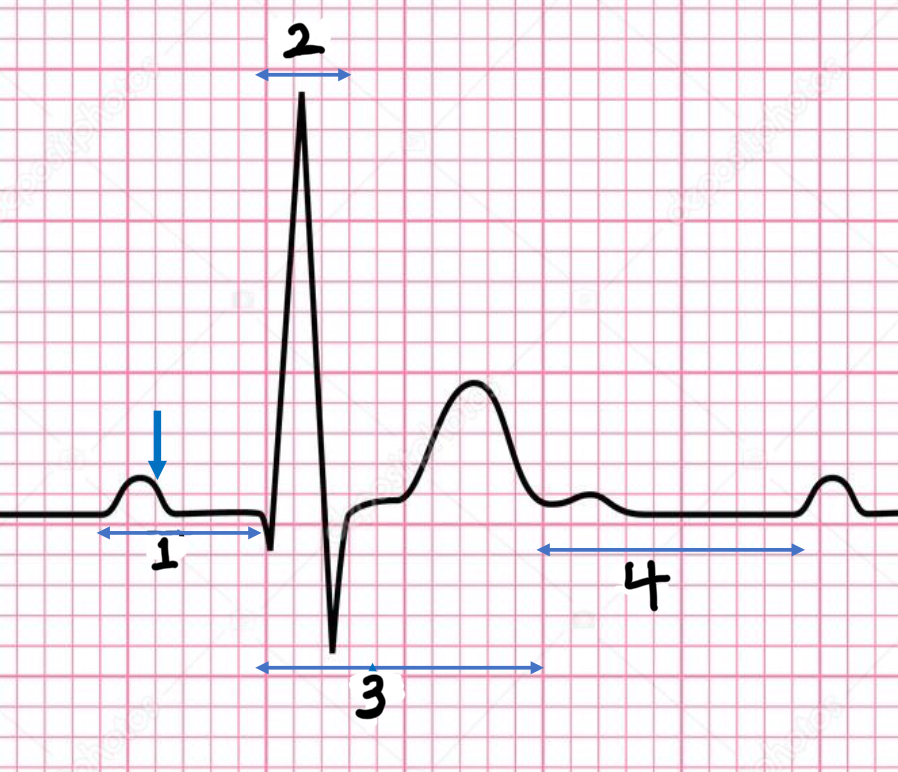

P wave

atrial depolarization

Precedes atrial contraction

QRS complex

ventricular depolarization

Precedes ventricular contraction

T wave

ventricular repolarization

PR interval

Name #1

QRS interval

Name #2

QT interval

Name #3

TP interval

Name #4

PR interval

time from beginning of the P wave to the beginning of the QRS complex

QRS interval

Time from beginning of the QRS complex to the end of the QRS complex

QT interval

Time from beginning of QRS complex to the end of the T wave

TP interval

Time from end of T wave to the beginning of P wave